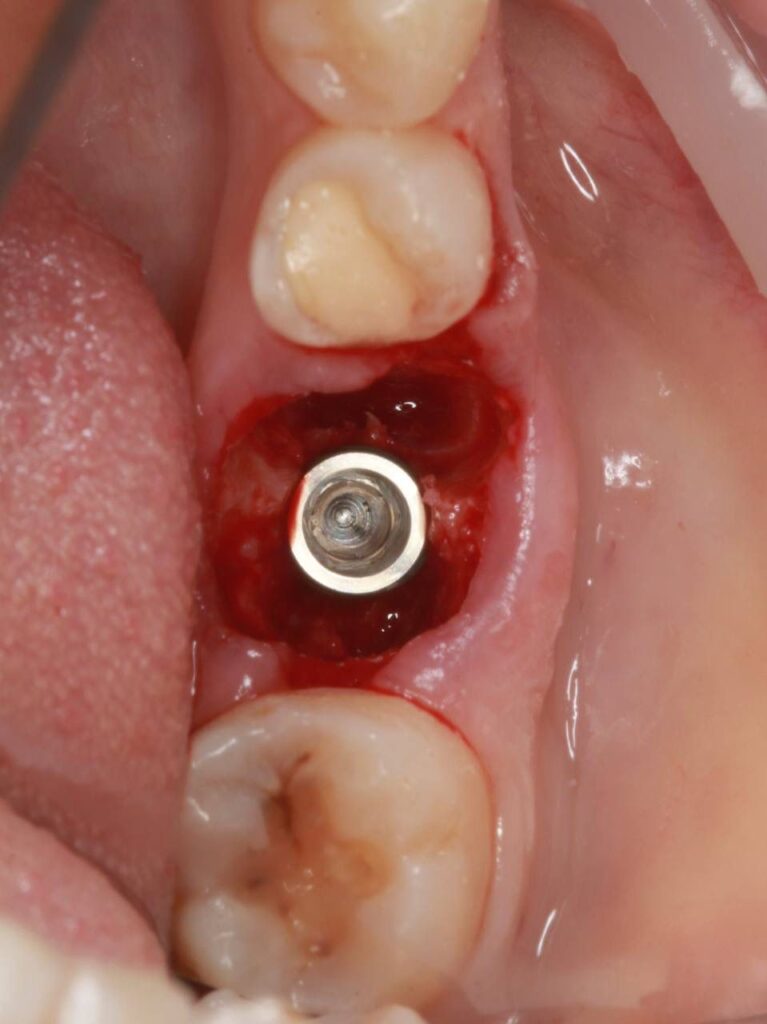

Специализация: терапия(эндодонтия), ортопедия, имплантология.